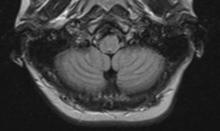

New results in animals highlight a major safety concern regarding a class of magnetic resonance imaging (MRI) contrast agents used in millions of patients annually, according to a new paper. The paper was published online by the journal Investigative Radiology, which is published by Wolters Kluwer.